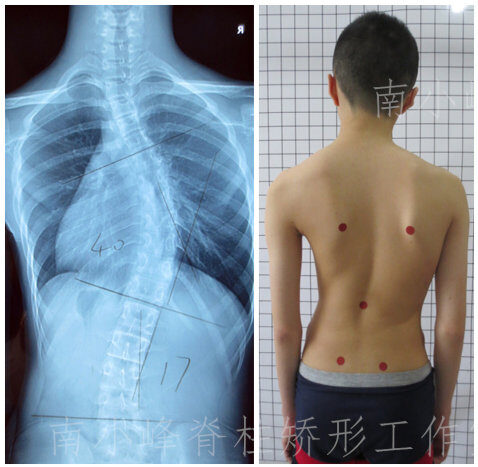

هل اعوجاج العمود الفقري يسبب ألماً عند الأطفال؟ أعرف الأعراض والعلاج المبكر يُعدّ اعوجاج العمود الفقري، أو ما يُعرف بالجنف، من المشكلات الشائعة بين الأطفال والمراهقين. كثير من الأهل يلاحظون انحناء غير طبيعي في

أهمية علاج اعوجاج العمود الفقري مبكرا عند للأطفال | كيف تمنع الجراحة وتحمي طفلك احذر… التطور سريع، والعلاج المبكر هو الحل هل سمعت من قبل نصيحة تقول: “لننتظر ونرى” عندما شككت بوجود اعوجاج في

الفحص المبكر لاعوجاج العمود الفقري: سر تجنب الجراحة وخفض التكاليف للأطفال والمراهقين اعوجاج العمود الفقري أو الجنف من المشكلات الصحية التي قد تظهر في سن مبكرة، خصوصًا عند الأطفال والمراهقين. الكثير من الأهل والمرضى

أخطاء شائعة عند ارتداء حزام اعوجاج العمود الفقري (الجنف) وكيفية تجنبها لضمان أفضل نتائج استخدام حزام اعوجاج العمود الفقري هو من أكثر الطرق الفعالة لعلاج الانحناءات الخفيفة والمتوسطة عند الأطفال والمراهقين. لكن الالتزام بطريقة